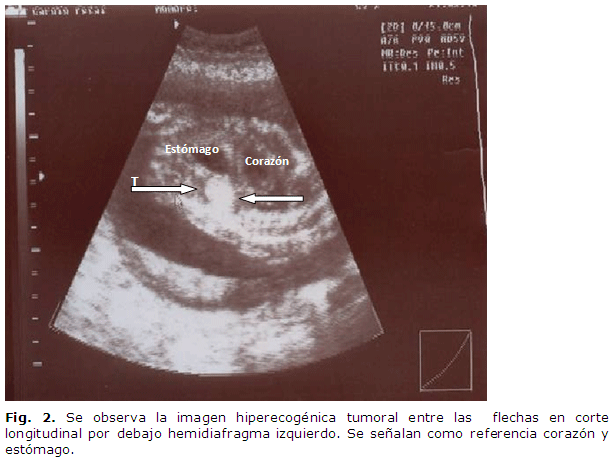

El día 24 de mayo acude para que se le realice dicho examen, y se encuentran ambos ecocardiograma fetales normales, pero se decide realizar ecografía completa, donde se encuentra en el primer gemelar una tumoración hiperecogénica de forma triangular que mide 15 X 12 mm por encima del polo superior del riñón izquierdo y por debajo del diafragma. El resto del examen de ese feto era normal. (Figura 1 y Figura 2).

En el otro feto se encontró un quiste del polo superior del riñón derecho sin otras alteraciones. Dado los hallazgos ecográficos se planteó en el primer feto que la imagen tumoral observada podía estar en relación con un tumor sólido de suprarrenal (neuroblastoma), y como diagnóstico diferencial un secuestro extralobar, que son los más frecuentes precisamente en la parte subdiafragmática izquierda.